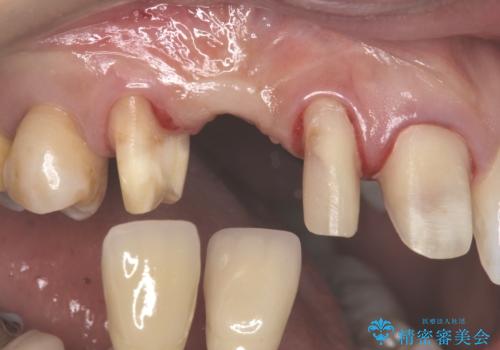

しっかり虫歯を取ったうえで、清掃性の高いブリッジにしていくことをおすすめしました。

右上④3②①ブリッジの設計としました。

右上2番単独の支台歯では不足のため、右上12とも支台歯にしています。